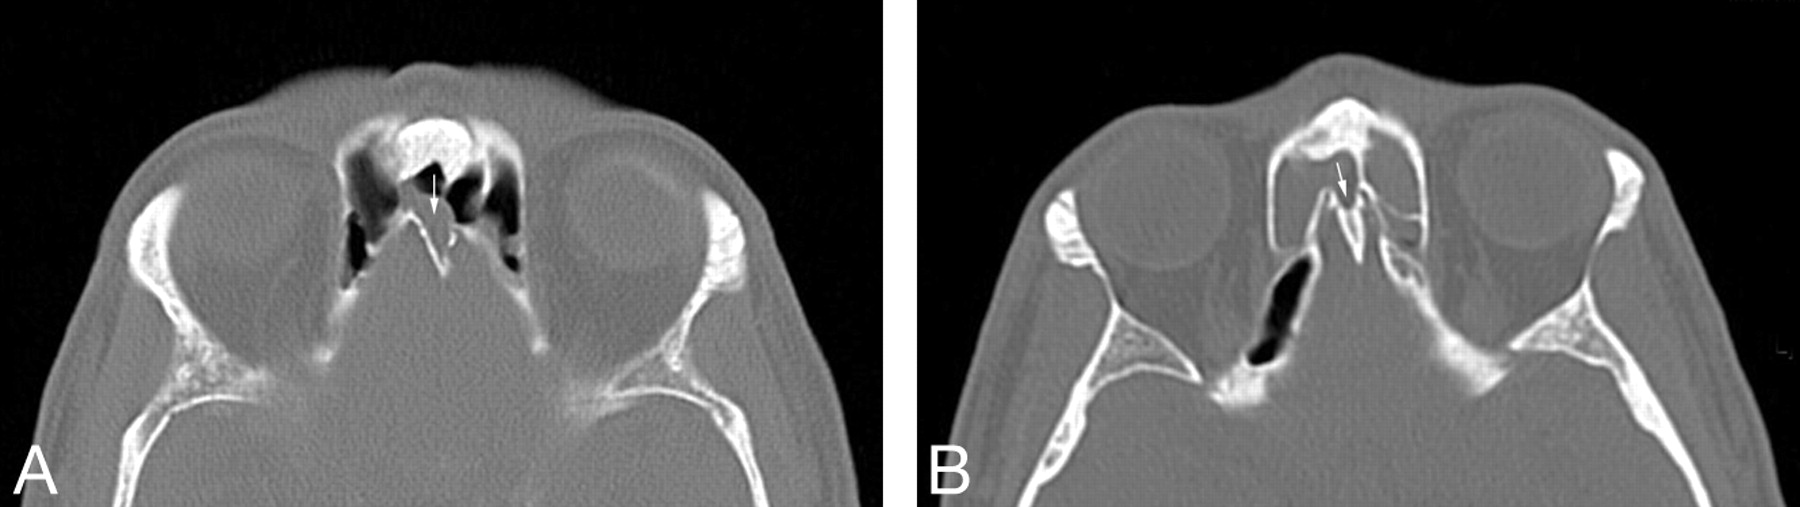

Of the 200 CT scans in adults, there were 26 with some degree of pneumatization of the crista galli (13%). There were 4 cases with only minimal pneumatization and 22 cases with extensive pneumatization (Fig 1). In all cases, the pneumatizing air cell was either the left (11 cases) or right (15 cases) frontal sinus and the crista galli was pneumatized from its anteriormost surface. In 2 cases, inflammatory disease in a frontal sinus extended directly into the pneumatized crista galli (Fig 2).

A, Axial CT scan of the paranasal sinuses in a 27-year-old man with sinus pain shows polypoid mucosal thickening extending from the right frontal sinus into a well-pneumatized crista galli (arrow). B, Axial CT scan of the paranasal sinuses in a 49-year-old woman with sinus pain shows extensive mucosal thickening extending from the right frontal sinus into a well-pneumatized crista galli (arrow). There is also mucosal disease in the left frontal sinus.